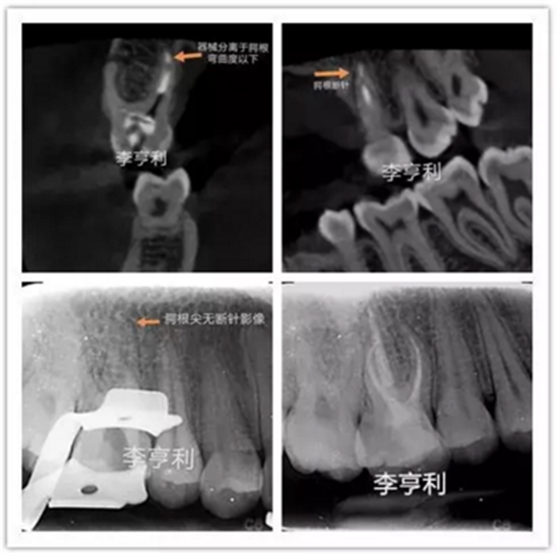

李亨利取出腭尖斷針的病例

在根管治療前,一定要充足地預估難度,謹記根管解剖,并且要熟悉自己臨床使用器械的設計、尺寸和參數(shù)。雖然說斷針本身并不影響治療效果,但往往都是因為患者的個人意愿,最后選擇取出斷針。如果難度超過術(shù)者自身的能力,就一定要轉(zhuǎn)診至??频难荔w牙髓醫(yī)生進行處理。